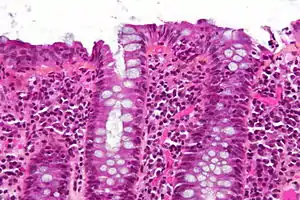

| Micrograph of lymphocytic colitis. HPS stain. | |

The colonoscopy is normal but histology of the mucosal biopsy reveals an accumulation of lymphocytes in the colonic epithelium and connective tissue (lamina propria). Collagenous colitis shares this feature but additionally shows a distinctive thickening of the subepithelial collagen table.[1][2]